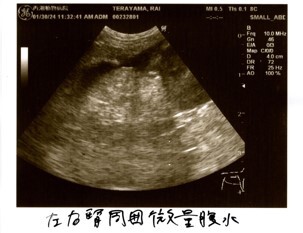

炎症の値は振り切れ、貧血、黄疸、リンパ節腫大、化膿性肉芽腫炎症という検査結果から、FIPを強く疑う。との診断でした。